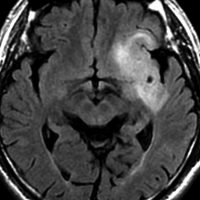

テモゾロマイド単独化学療法の例

2010年無症状の時の画像です。こんなのを手術で摘出したら認知機能が落ちて人格が変わります。だから経過観察しました。

2015年のテモゾロマイドを開始する前の画像です。2014年にちょびっと生検術をして1p/19q欠失,IDH変異はわかっていました。2015年に全般発作を起こしたので治療を開始しました。テモゾロマイドを 2年 24コース続けました。乏突起膠腫は大きくなる時,てんかんを生じることが多いです。

2020年の画像です。腫瘍はかなり小さくなって再燃(再発)していません。てんかんも抑制されて発作はありません。無症状です。

この例は,手術も放射線治療もしないで,乏突起膠腫が10年以上,制御できることを示しています。また,テモゾロマイド治療でてんかん発作が少なくなることも有名な事実です。

でも,現実はこんなに甘くない?  2025年時点で,治癒を目指すなら低線量放射線治療を加えるべきと考えられています。